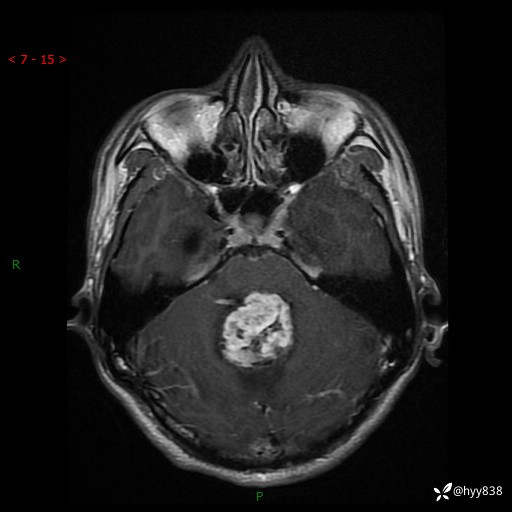

性别:男

年龄:17岁

简要病史:头痛伴间断性呕吐1月余,外院CT提示颅脑占位

颅脑MRI平扫+增强